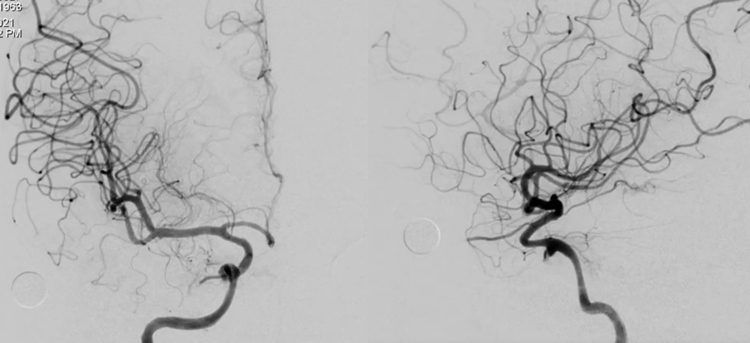

支架释放完后常规正侧位DSA造影显示血管形态良好,动脉瘤充盈明显减少。

双容积重建结果,显示支架和血管壁贴合非常好